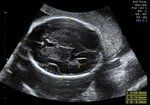

Presentation Scan

It is indicated when there is a concern about the position of the baby particularly if the midwife thinks that the baby is breech, transverse or oblique. A growth scan is performed with the presentation scan without any extra cost. We will be happy to give you one 2D image of your baby when possible, however, on some occasions this will not be possible due to fetal position.

• Wellbeing assessment includes position and Presentation of baby and placental position.

• Growth report includes estimated weight of baby at current gestation.

• Amniotic Fluid index measurement.

• Umbilical artery Doppler measurement.

• Middle Cerebral Artery Doppler measurement.